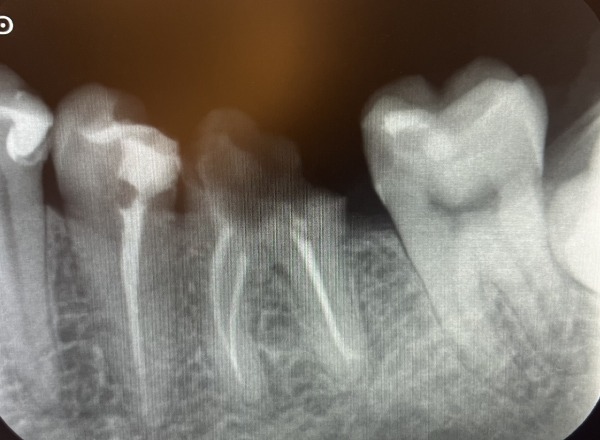

診察をしたところ、左下の奥歯2本が大きな虫歯になっていました。手前は歯の根っこだけになり、奥歯は大きく穴が開いていました。エックス線写真を撮ると、前医での根管治療後に被せ物が装着されないまま中断された状態が確認できました。また、奥歯を中心に何か所か歯と歯の間から虫歯ができていました。

1日目〜3日目 左下の歯の根管治療を行い、治療後のエックス線を撮影しました。

4日目 根管治療を終えた後に土台を立てました。